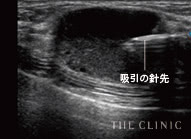

しこりを視覚化して丁寧に除去

脂肪注入豊胸やヒアルロン酸豊胸のしこりは、的確にアプローチしてこそ除去することができます。触診だけでの曖昧な見当で治療を行うクリニックもあるようですが、海外では「暗闇での手術」と言われ、とても危険視されている行為です。

その点、THE CLINIC では必ずエコーを併用。実際にしこりを目視しながら注射器や吸引管をピンポイントに挿入、除去できます。最短ルートのアプローチなので、体へのダメージを抑えることができる点もメリットです。

実際のエコー画像

吸引中